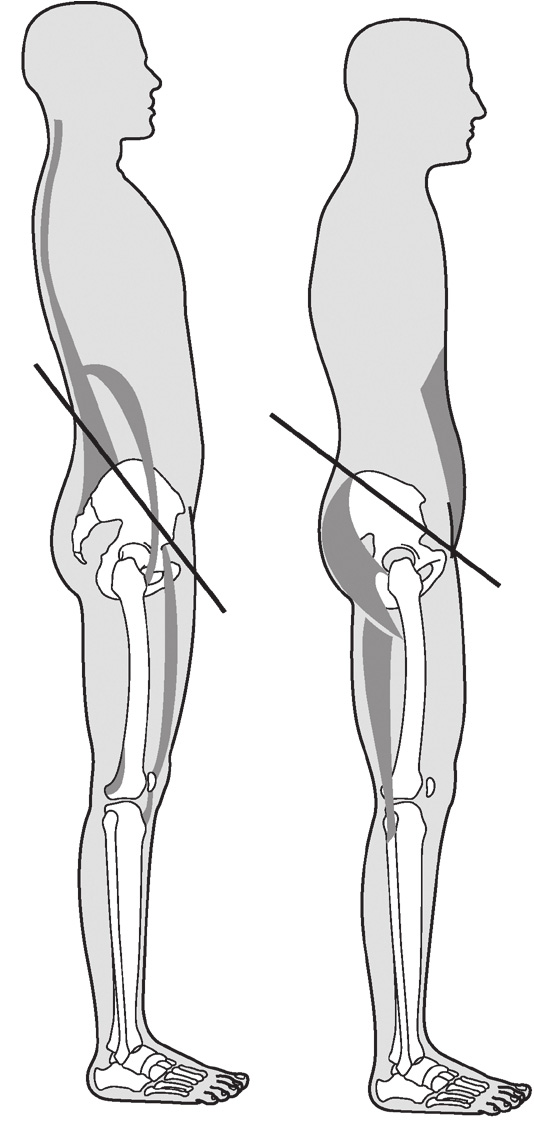

骨盆前倾/骨盆后倾(图2.1)

以髂前上棘(anterior superior iliac spine,ASIS)位置为参考点的动作。骨盆后倾(posterior pelvic tilt,PPT)是减少腰椎前凸使腰椎变得平坦,并将髋关节向前移。骨盆前倾(anterior pelvic tilt,APT)则是增加腰椎前凸(图2.1)

图2.1 骨盆前倾与骨盆后倾的机制